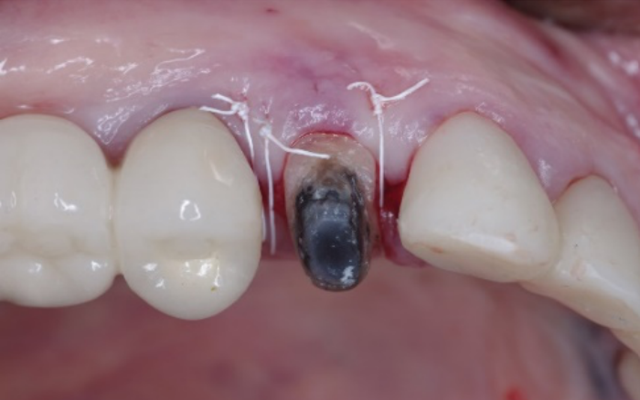

Functional crown lengthening is required if there is insufficient tooth structure to enable your dentist to provide a retentive and long-lasting restoration (Figures 9B & C). This may be because your tooth is broken, worn, or cracked or if there is extensive decay extending below the gum line.

Crown lengthening to expose more sound tooth structure.

Your periodontist will assess whether there is sufficient crown and root structure left to benefit from crown lengthening, and then advise you on the details of the procedure as well as the outcome. The crown lengthening procedure is normally carried out under local anaesthetic. It may involve removal of some of the gum and/or underlying bone. As it is a minor surgical procedure stitches are often used. The number of teeth that need treatment as well as the amount of gum repositioning will affect the healing time.